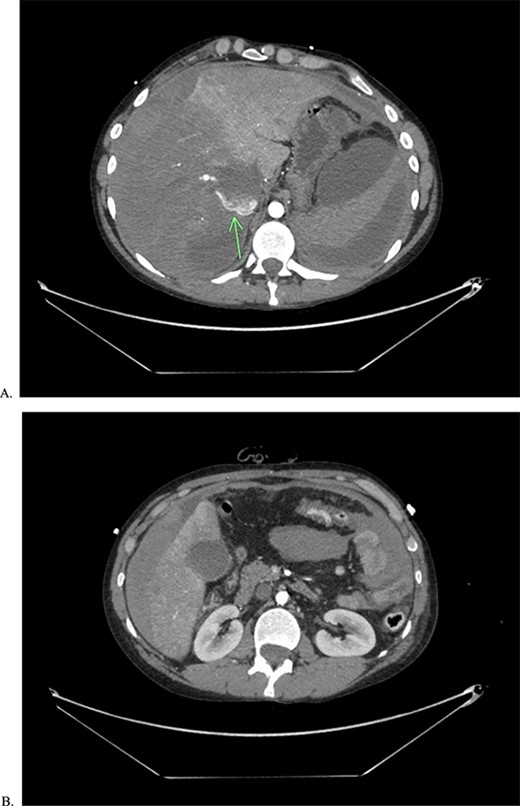

He returned to the ED on POD 9 with episodes of emesis and abdominal pain. En route, he was hypotensive and had a coughing spell with witnessed evisceration. The initial workup included a FAST (focused assessment with sonography in trauma) exam which was positive for free fluid in the abdomen. Massive transfusion protocol (MTP) was initiated, and the patient was sent for CT angiogram of the chest, abdomen, and pelvis en route to the OR. The scan revealed a large area of contrast extravasation in the right hepatic lobe with a significant amount of free fluid (Fig. 2).

CTA of abdomen and pelvis showing the large contrast extravasation (A) as well as significant amount of free fluid in the abdomen (B).